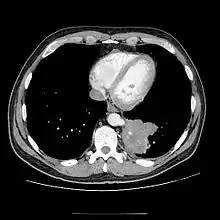

CT

- CT scans have 90% accuracy in the diagnosis of pulmonary sequestration.

- The most common appearance is a solid mass that may be homogeneous or heterogeneous, sometimes with cystic changes.

- Less frequent findings include a large cavitary lesion with an air-fluid level, a collection of many small cystic lesions containing air or fluid, or a well-defined cystic mass.

- Emphysematous changes at the margin of the lesion are characteristic and may not be visible on the chest radiograph.

- CT technique for optimal depiction of lesions by using state-of-the-art volumetric scanning requires a fast intravenous (IV) contrast injection rate and appropriate volume and delay based upon size.

- Multiplanar and 3D reconstructions are helpful.